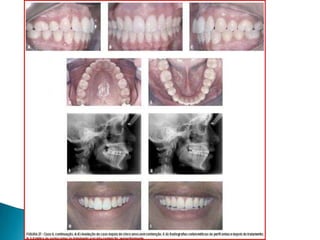

   Figura 1.,2

Figura 1.,2